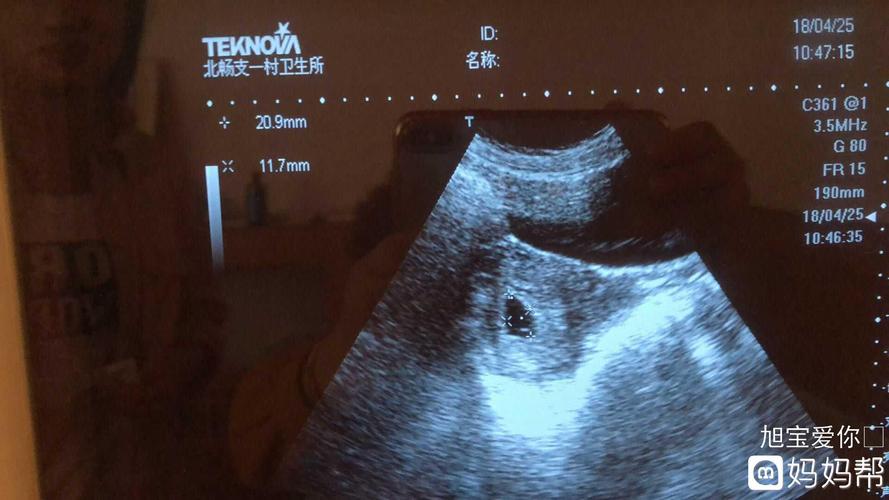

根据一些传言,有人相信孕囊的大小与胎儿性别有关。据说,如果孕囊的长和宽差距超过一倍,那么男宝宝的可能性较大。相反,如果孕囊的长和宽相等,或者差距不大,那么很可能是个女宝宝。一些妈妈回顾当年怀孕时进行的B超检查数据,发现了对应的情况。例如,有一位妈妈在怀孕8周时,孕囊的大小是16mm×17mm,结果生下了一个小公主。

还有一种说法认为,通过观察孕囊的形状可以判断胎儿的性别。一般来说,如果孕囊呈茄子形状或长条状,那么怀上男宝宝的可能性较大。而如果孕囊呈椭圆形或圆形,那么很可能是个女宝宝。

根据一些传言,有人相信孕囊的大小与胎儿性别有关。据说,如果孕囊的长和宽差距超过一倍,那么男宝宝的可能性较大。相反,如果孕囊的长和宽相等,或者差距不大,那么很可能是个女宝宝。一些妈妈回顾当年怀孕时进行的B超检查数据,发现了对应的情况。例如,有一位妈妈在怀孕8周时,孕囊的大小是16mm×17mm,结果生下了一个小公主。

还有一种说法认为,通过观察孕囊的形状可以判断胎儿的性别。一般来说,如果孕囊呈茄子形状或长条状,那么怀上男宝宝的可能性较大。而如果孕囊呈椭圆形或圆形,那么很可能是个女宝宝。